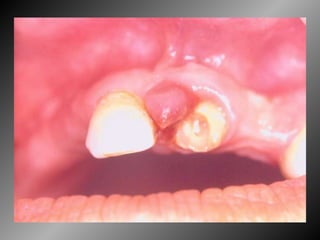

Granuloma Piogênico Lesão Nodular Séssil ou pediculada Avermelhada ou vinhosa Sangramento espontâneo e áreas de micro-ulceração superficial

Granuloma Piogênico Lesões nodulares de coloração avermelhada ou vinhosa Provavelmente uma reação inflamatória exagerada ao trauma menor Crescimento rápido, às vezes sangramento espontâneo Ocorre em qualquer idade mas parece mais freqüente em adultos jovens e adolescentes  Localização mais comum: gengiva (NEVILLE,2001)

Granuloma Piogênico Lesões mais antigas, são menos vasculares e mais fibrosas Papila interdental e regiões anteriores são áreas preferenciais, principalmente por vestibular (BORK,1996)

25 - L.C.S., sexo masculino, 18 anos de idade, se apresentou com queixa de aumento de volume na gengiva entre os dentes 23 e 24. Pelo exame clínico, constatamos a presença de um nódulo séssil, de contornos irregulares, coloração avermelhada, com sangramento abundante ao mínimo toque e evolução de 1 ano. O paciente apresentava higiene bucal precária com presença de placa bacteriana e tártaro. Com base no quadro clínico, o diagnóstico é: a) Fibroma e granuloma piogênico. b) Granuloma piogênico e hiperplasia fibrosa inflamatória. c) Lesão periférica (granuloma) de células gigantes e fibroma. d) Granuloma piogênico e lesão periférica (granuloma) de células gigantes. e) Hiperplasia fibrosa inflamatória e fibroma.

Granuloma Piogênico LesãoNodular Séssil ou pediculada Avermelhada ou vinhosa Sangramento espontâneo e áreas de micro-ulceração superficial

Granuloma Piogênico Lesõesnodulares de coloração avermelhada ou vinhosa Provavelmente uma reação inflamatória exagerada ao trauma menor Crescimento rápido, às vezes sangramento espontâneo Ocorre em qualquer idade mas parece mais freqüente em adultos jovens e adolescentes Localização mais comum: gengiva (NEVILLE,2001)

Granuloma Piogênico Lesõesmais antigas, são menos vasculares e mais fibrosas Papila interdental e regiões anteriores são áreas preferenciais, principalmente por vestibular (BORK,1996)